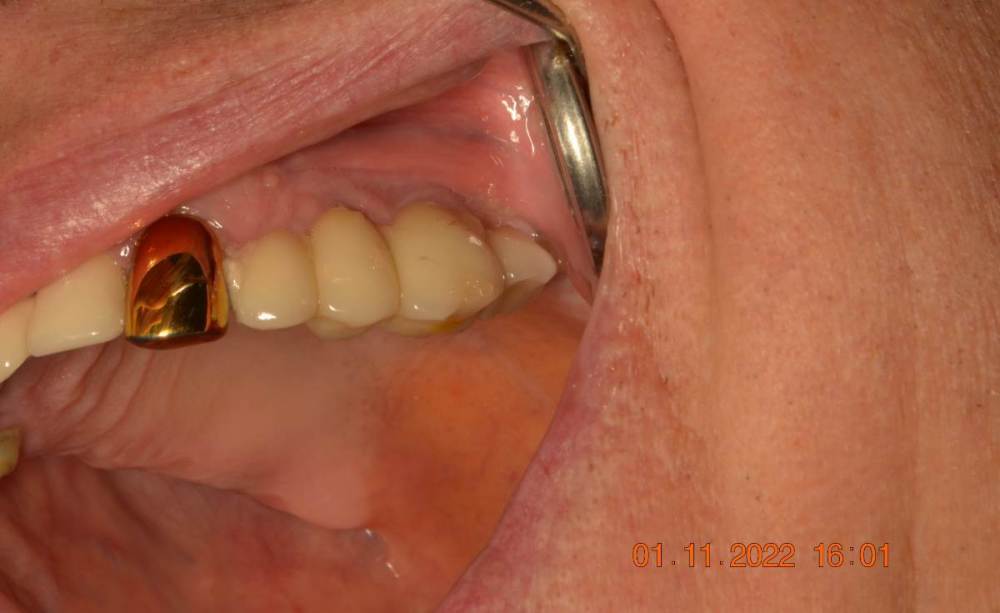

Большой Зеленый Опубликовано 7 ноября, 2022 Поделиться Опубликовано 7 ноября, 2022 Обратите внимание на даты 2 Ссылка на комментарий

TIGER Опубликовано 7 ноября, 2022 Поделиться Опубликовано 7 ноября, 2022 @Большой Зеленый оригинал нужен только(я не использую реплики например ),плюс в РФ и мире и система не распостранена.за этот прайс есть куча систем более продвинутых . Ссылка на комментарий

Большой Зеленый Опубликовано 7 ноября, 2022 Поделиться Опубликовано 7 ноября, 2022 У дилера есть премил абатменты. За 10 лет работы проблем никаких не было. 1 Ссылка на комментарий